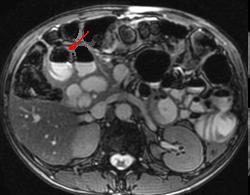

| Deux diverticule du bord

interne de D2 . Image IRM + enteroclyse |

Meme en TDM ( fleche rouge ) |